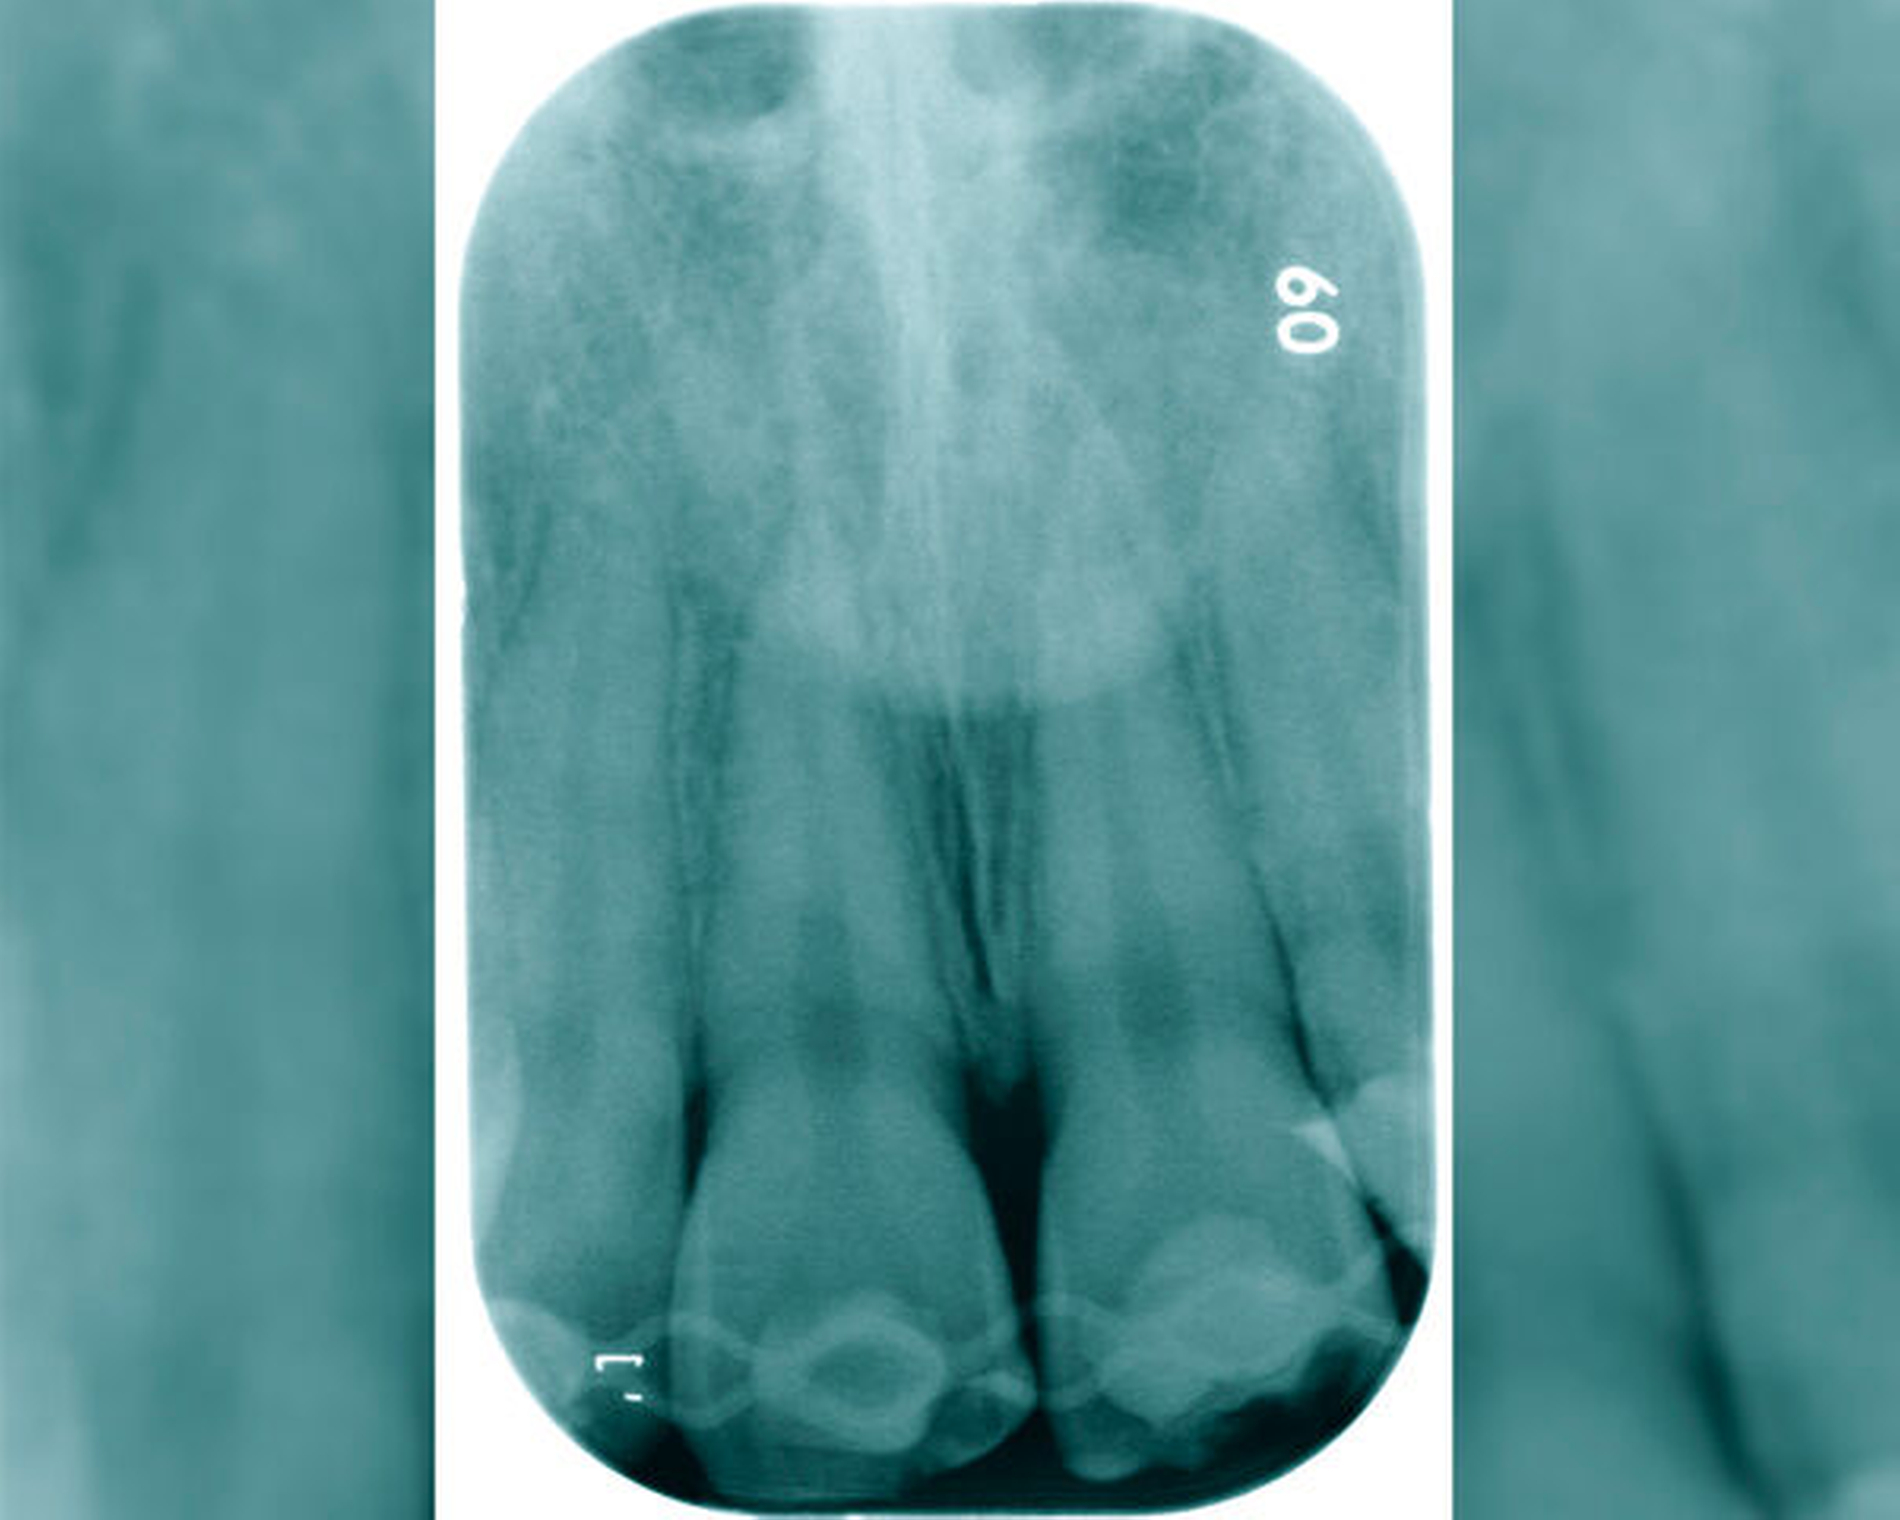

Zusätzlich zur endodontischen Therapie ist eine unterstützende antibiotische Therapie bei den folgenden Fällen nicht indiziert [Segura-Egea et al., 2017; Segura-Egea et al., 2021¸ Longman et al., 2000]:

Symptomatische irreversible Pulpitis (Abbildung 3)